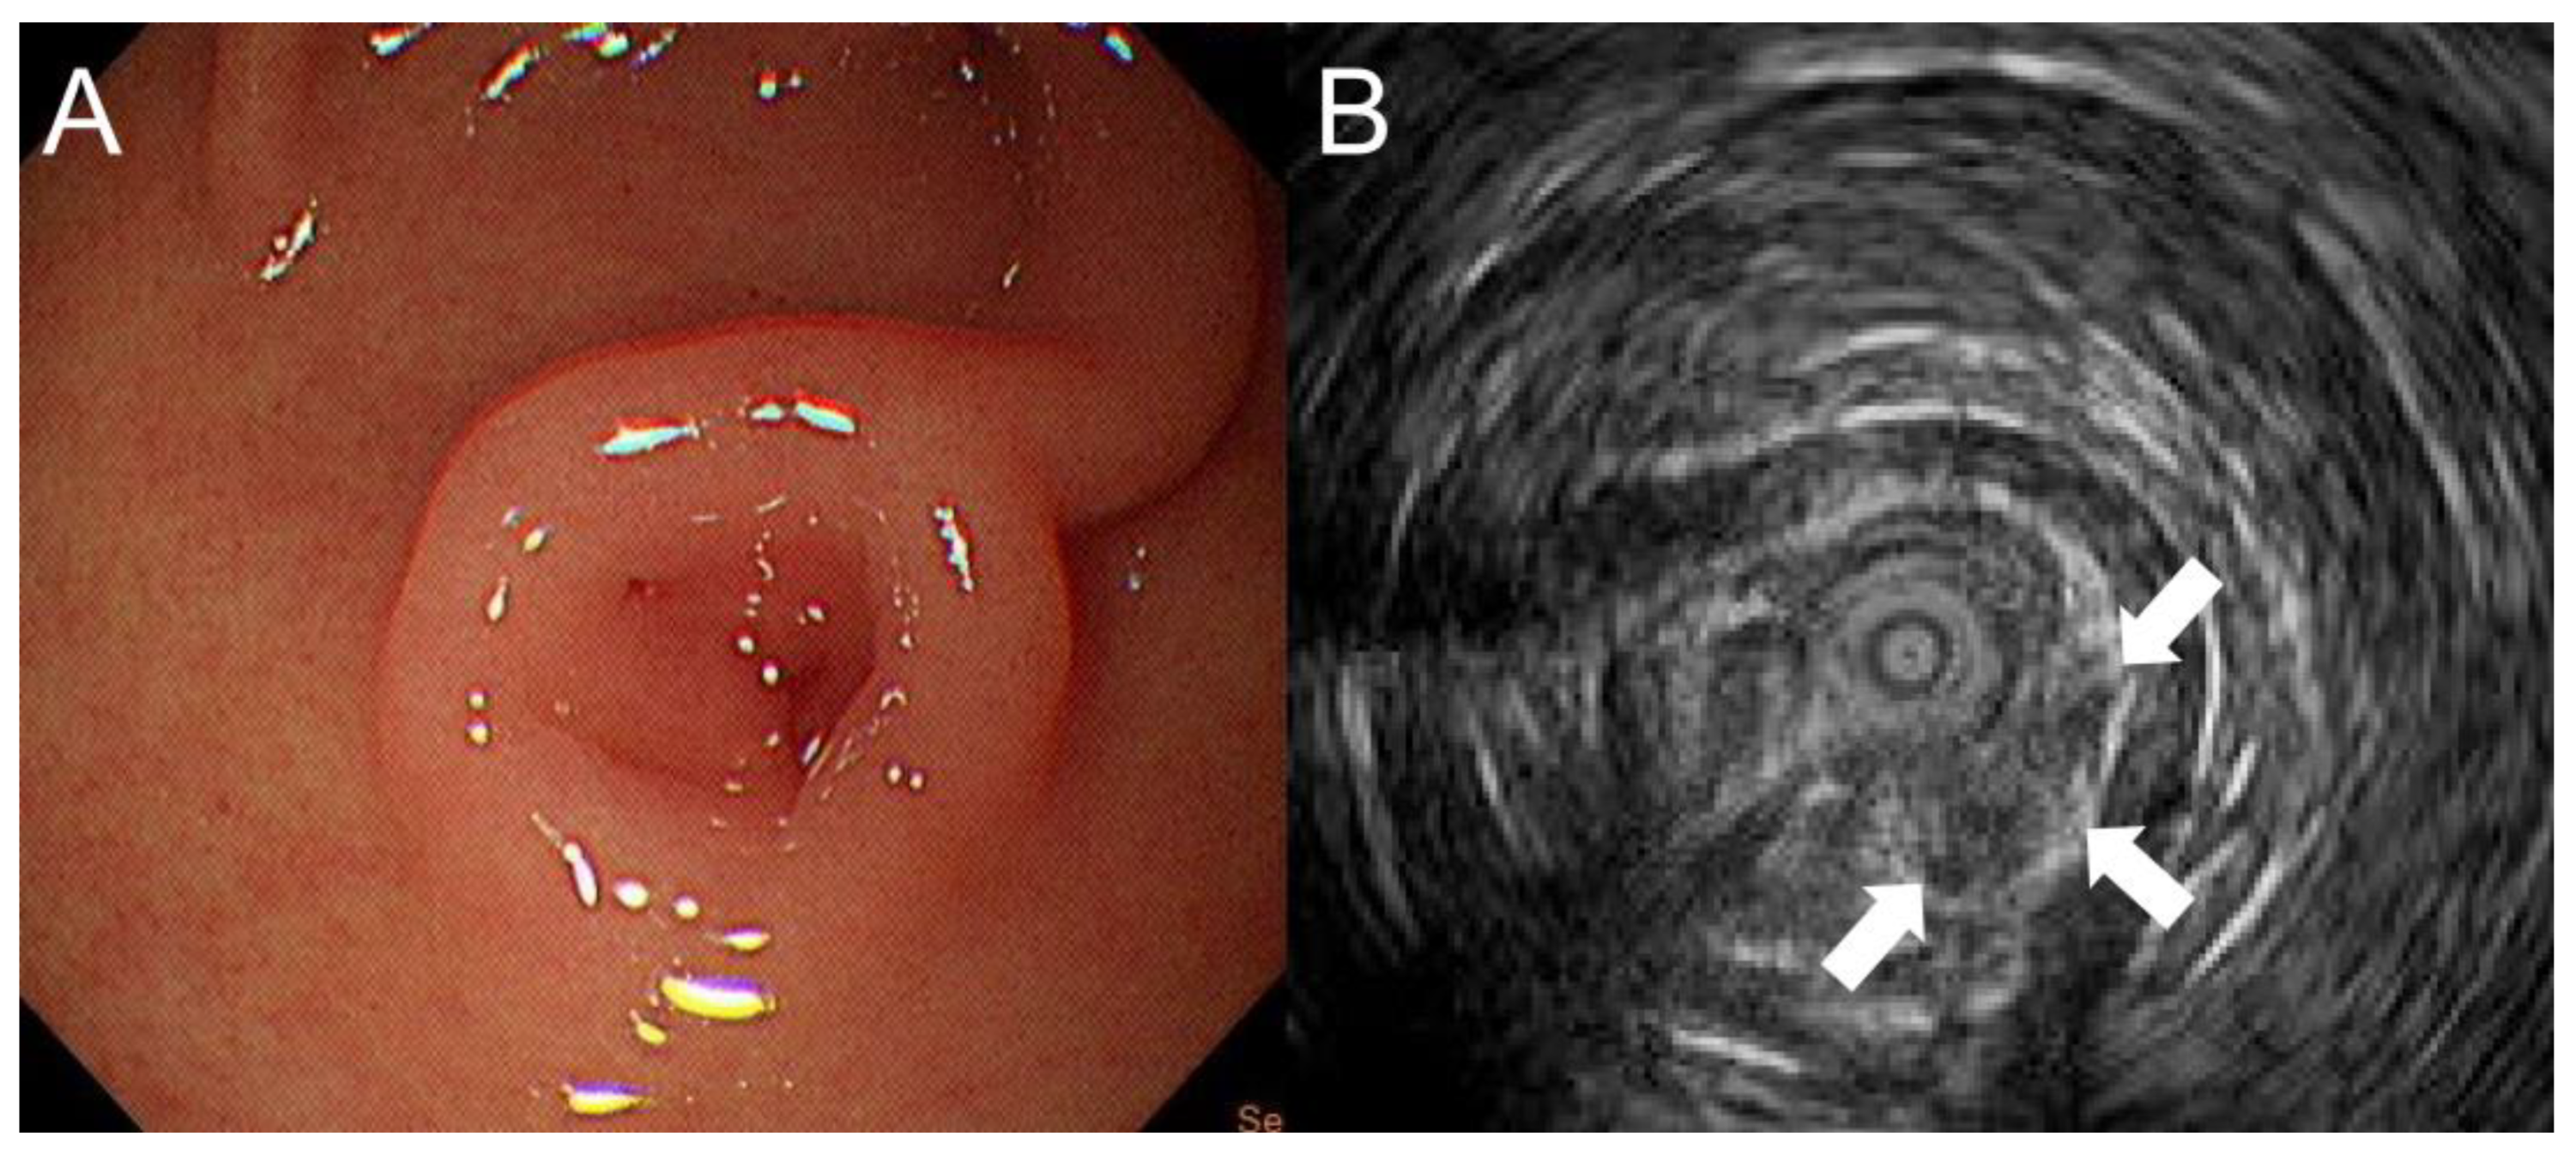

A 13-year-old boy presented to our hospital with a 3-month history of recurrent episodes of epigastric pain and a 1-week history of watery diarrhea with a frequency of 10 times a day, without blood or mucus. He had no nausea or vomiting but had weight loss of 4.2 kg within 2 months. Physical examination and plain abdominal X-rays were unremarkable and non-diagnostic. Laboratory studies including amylase, lipase and gastrin were normal. Stool culture and rotavirus antigen tests were negative. EGD revealed one oval subepithelial lesion with central umbilication located in the gastric antrum measuring approximately 10 mm in diameter (Figure 1A). The gastric mucosa appeared normal. HP was suspected. However, endoscopic conventional biopsy of the lesion showed chronic gastritis. Endoscopic ultrasonography revealed that the lesion was hypoechoic, heterogeneous with ill-defined margins, measuring 4.8 × 2.7 mm in size, arising from the submucosa (Figure 1B). A repeat endoscopic conventional biopsy of the lesion again showed chronic gastritis. Computed tomography of the abdomen revealed mild polypoid wall thickening, measuring 11 mm in diameter, located in the anterior wall of the gastric antrum. Laparoscopic resection of the lesion was arranged. Under general anesthesia, pediatric gastroscope (EG-760R, Fujifilm, Tokyo, Japan) was inserted through the mouth into the stomach. Endoscopic tattooing was performed by a pediatric gastroenterologist with a carbon-particle-containing solution, SPOT®, without dilution. The 23-gauge injection needle (Top Endoscopic Puncture Needle Digestive Tract, Top Surgical Taiwan Corporation, Kaohsiung, Taiwan) was punctured as perpendicularly as possible at four quadrants of the tumor deep into the muscle layer. Initially, 0.5 mL of SPOT® was injected at the distal edge of the lesion. There was slight overflowing of the dye in the mucosa. This was followed by 0.3 mL of SPOT® injected over the other 3 quadrants of the lesion (Figure 2A). Endoscopic tattooing was followed by laparoscopic resection of the lesion. The tattooing was seen near the antrum of the stomach (anterior surface) (Figure 2B). Gastrotomy was performed, and full thickness excision of the tumor was performed. The final pathology report confirmed the presence of heterotopic pancreatic tissue including pancreatic acini, small pancreatic ducts tissue with islets of Langerhans in the deep gastric submucosal area (Figure 3A,B). The patient was discharged 6 days after surgery without postoperative complications. He remained symptom free 1 year after surgery.

Figure 1.

(A) Esophagogastroduodenoscopy revealing one oval subepithelial lesion with central umbilication located in the gastric antrum measuring approximately 10 mm in diameter. (B) Endoscopic ultrasonography showing that the lesion was hypoechoic, heterogeneous with ill-defined margins, measuring 4.8 × 2.7 mm in size, arising from the submucosa (arrow).